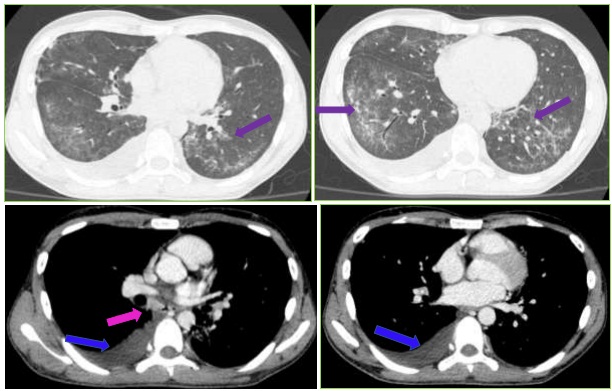

Hình ảnh Cắt lớp vi tính lồng ngực:

Hình 3: Đám đông đặc, kính mờ 2 phổi – theo dõi viêm (mũi tên tím). Tràn dịch màng phổi phải dày ~ 16mm (mũi tên xanh lam). Vài hạch trung thất, lớn nhất 12x11mm (mũi tên hồng)

Hình ảnh Cắt lớp vi tính ổ bụng:

Hình 4: Không thấy hạch bất thường ổ bụng và tiểu khung. Nang nhỏ gan phải. Lách to